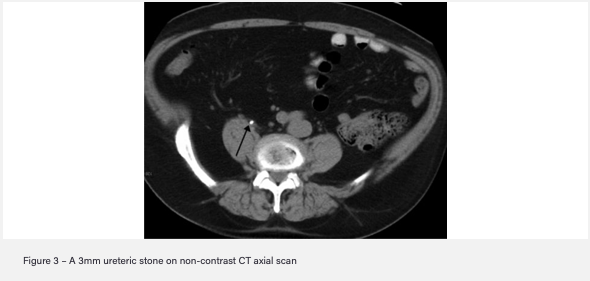

- Gold standard imaging: Non-contrast CT KUB

- Other imaging: AXR with IV urogram (most stones not radiolucent and high radiation exposure) or US to assess for hydronephrosis